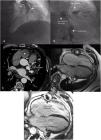

A 63-year-old male, with type 2 diabetes, hypertension and atrial fibrillation, presented with complaints of typical angina. The electrocardiogram and transthoracic echocardiogram were unremarkable. He began antianginal drugs and was referred for an elective coronary angiography that showed multiple giant aneurysms on both coronary arteries (Figure 1, panels A and B). A computed tomography coronary angiography was performed confirming the presence of multiple coronary aneurysms, the largest on the right coronary artery (RCA, 45 mm), followed by the left anterior descendant (LAD, 17 mm) and circumflex (Cx, 15 mm) arteries (Figure 1, panel C). A cardiac MRI scan was performed, showing the presence of coronary aneurysms in the cine sequences (Figure 1, panel D) with thrombi in the cavity of the aneurysms seen in the late gadolinium enhancement sequences (Figure 1, panel E); interestingly, no myocardial infarctions were noted.

Giant coronary aneurysms seen by invasive coronary angiography (panels A and B), computed tomography coronary angiography (panel C) and cardiac MRI bSSFP cine (panel D) and late gadolinium enhancement (panel E), the latter revealing thrombi in the circumflex and right coronary arteries. bSSFP: balanced Steady-State Free Precession; Cx: circumflex artery; LAD: left anterior descendant artery; RCA: right coronary artery.